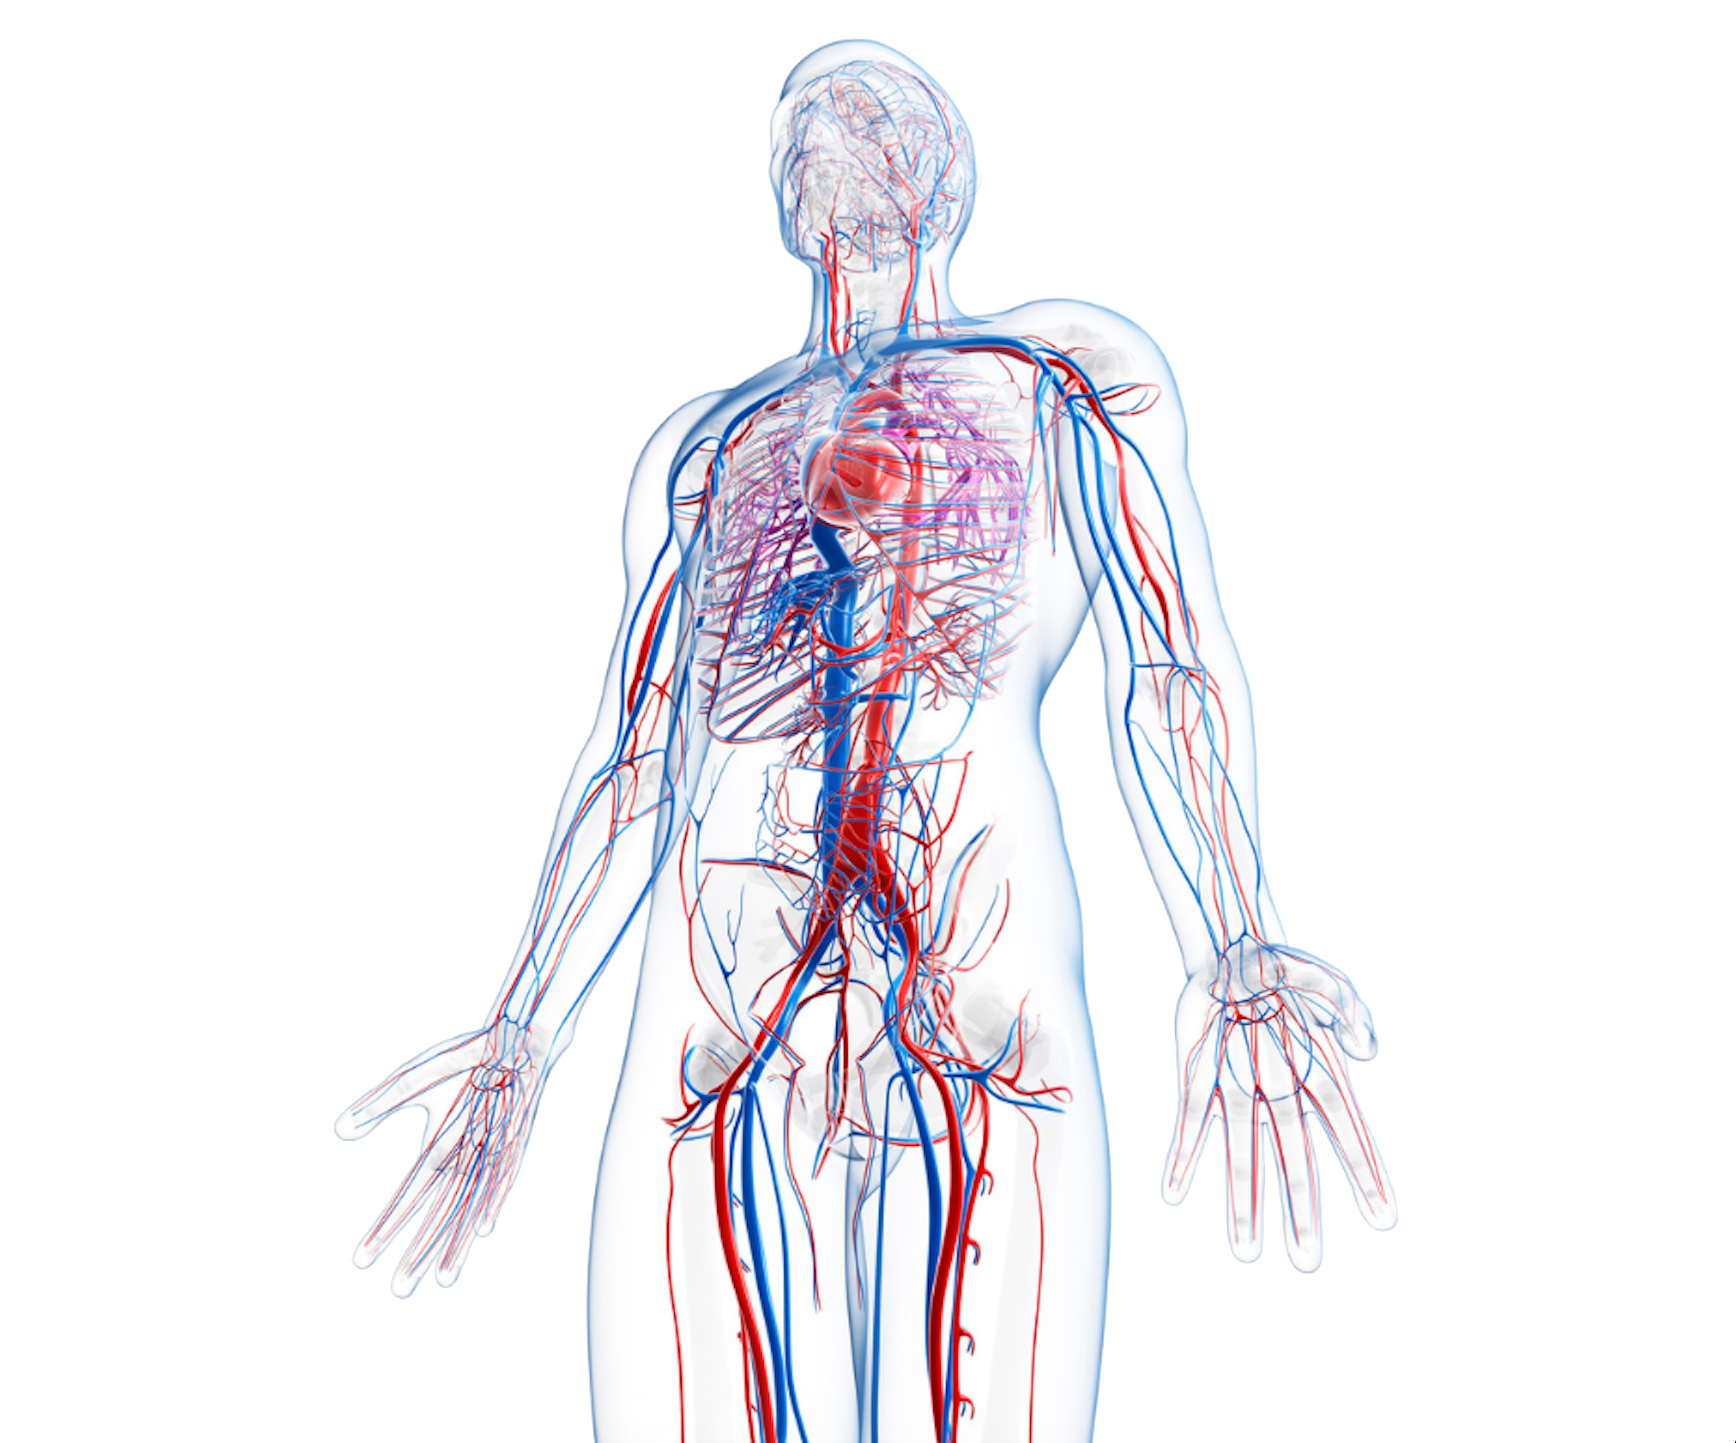

Vascular health & Cardiac Risk assessment

Early detection of peripheral arterial disease (PAD) & endothelial dysfunction

Non-invasive markers for arterial stiffness and microvascular health

Arterial Brachial Index (ABI)

Advanced screening for metabolic health and vascular function

Non-invasive diagnostics to enhance care